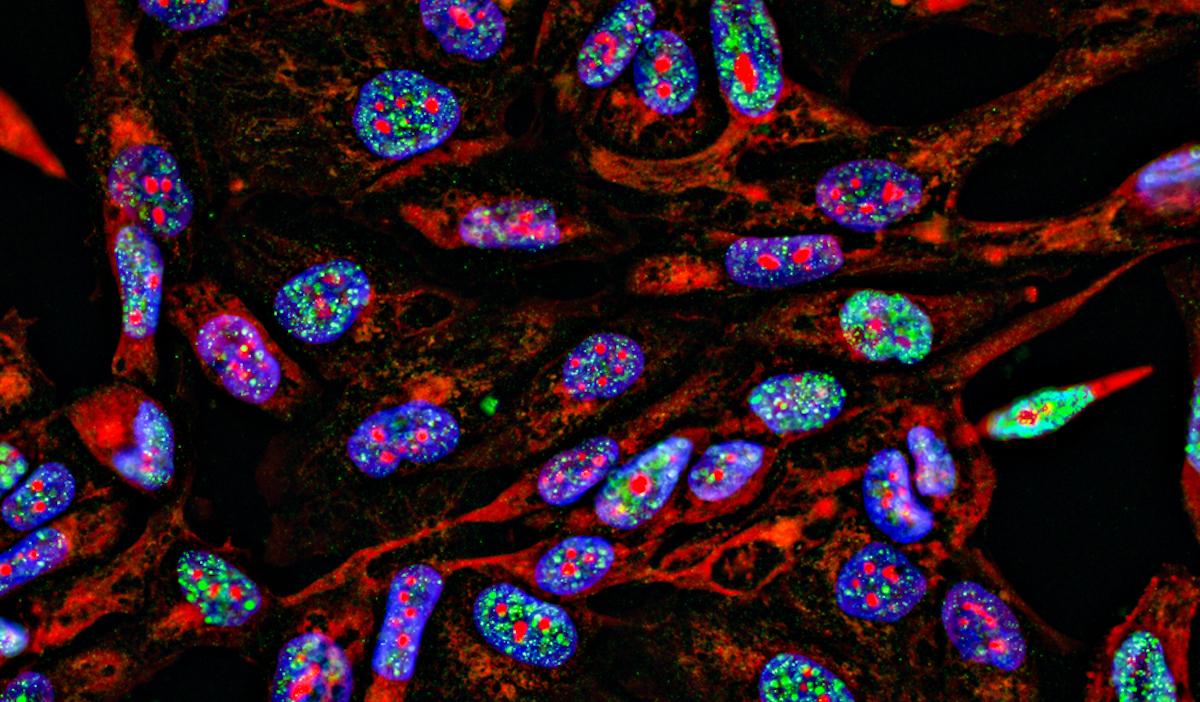

Sur un total de 511 patients traités, soit par chirurgie d’exérèse d’emblée, soit par chirurgie après une chimiothérapie néoadjuvante, l’analyse post-opératoire du microenvironnement immunitaire a été réalisée. Cette analyse comportait une analyse génomique, transcriptomique, ainsi qu’une description des cellules immunitaires.

Augmentation de l’infiltration en lymphocytes clés

La chimiothérapie néoadjuvante a été associée à une augmentation de l’infiltration en lymphocytes T CD8+ cytotoxiques ainsi qu’en lymphocytes B dans le microenvironnement immunitaire sur les pièces opératoires.

De plus, le microenvironnement immunitaire tumoral post chimiothérapie néoadjuvante comportait une plus grande quantité de lymphocytes T mémoires CD4+ et CD8+ comparativement au microenvironnement immunitaire des tumeurs opérées d’emblée.